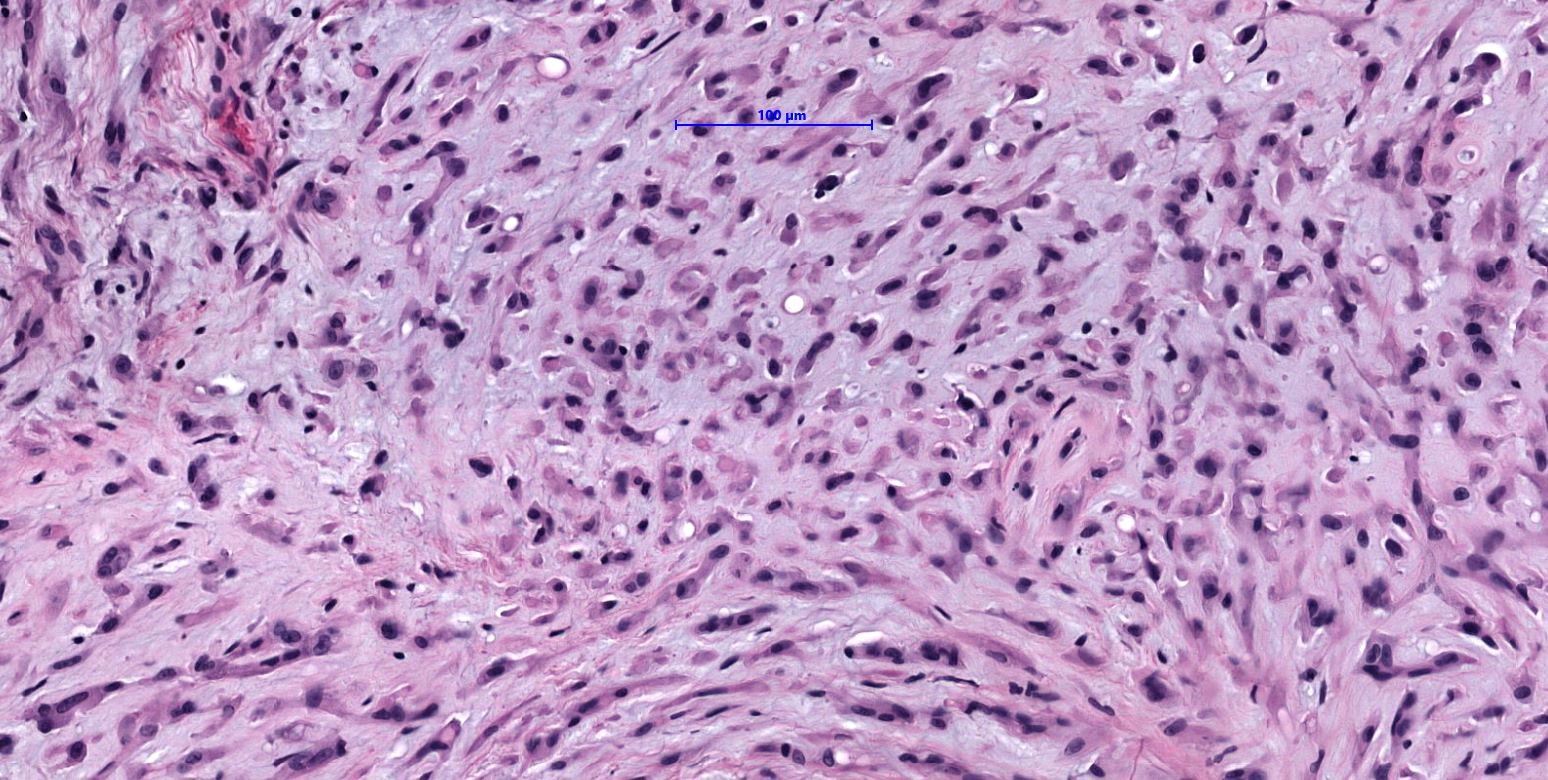

- WWTR1-CAMTA1 subtype (classic EHE):

- Cords, strands or small nests of large endothelial cells with abundant eosinophilic cytoplasm embedded in a myxohyaline stroma

- Tumor cells have vesicular, round to oval, sometimes indented nuclei

- Some tumor cells have intracytoplasmic, round, clear vacuoles representing small vascular lumina, which may contain erythrocytes

Microscopic (histologic) images